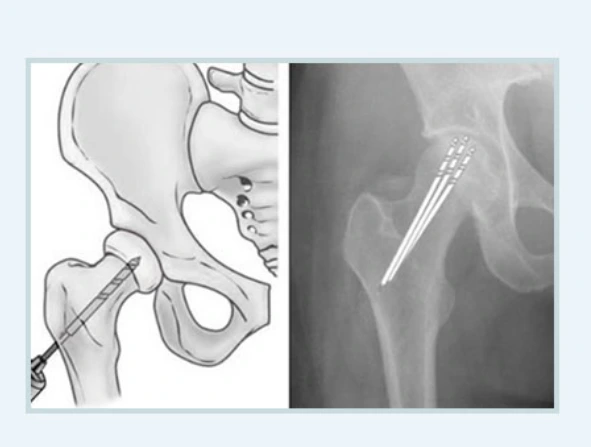

다발성 천공술

비교적 초기에 진행할 수 있는 간단한 수술로 대퇴골두에 구멍을 뚫어 내압을 낮추는 수술입니다. 초기에 시행한다면 50~70% 정도로 괴사를 예방해 줄 수 있지요.

다발성천공술.PNG